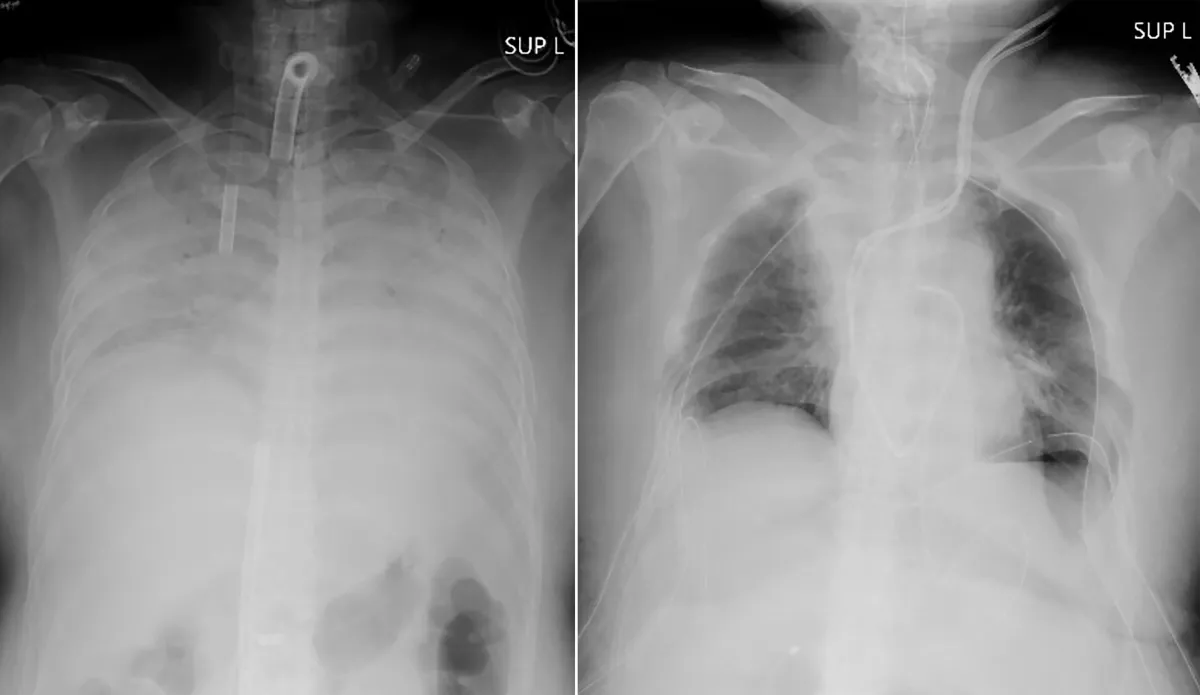

ويمكن أن يسبب Covid-19 تلفًا حادًا في الرئة لدى بعض المرضى، كما حدث مع هذه المريضة وقد خضع الناس في جميع أنحاء العالم لعمليات زرع الرئة كجزء من تعافيهم.

لكن مستشفى كيوتو قال إنها نجحت في أول عملية زرع أنسجة رئوية في العالم من متبرعين أحياء لمريض كوفيد 19 مصاب بتلف في الرئة.